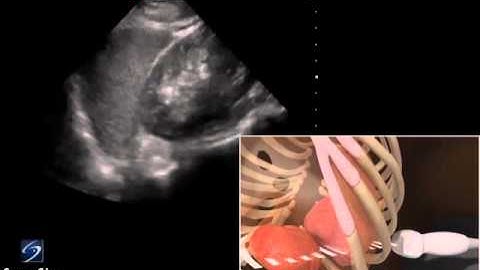

3D How to EFAST Lung Sliding Detection with Phased Array Transducer YouTube